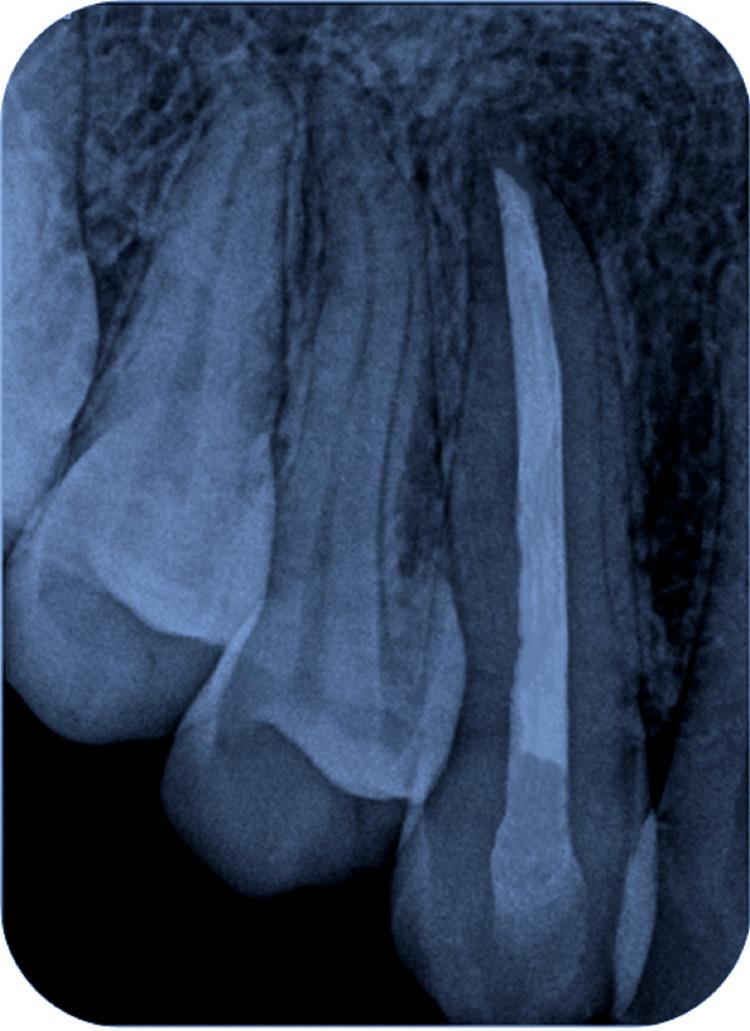

牙髓感染主要涉及革兰氏阴性厌氧菌菌群,由于这种感染,根尖周区域会发生免疫反应,这被称为根尖周病变。这种病变在X射线上可能表现为透射(暗)区,表明根尖周炎症和感染。其患病率取决于年龄、口腔卫生维护和牙科护理等因素。男性比女性更容易受到这种感染的影响。根尖周病变有两种治疗方式:手术或非手术牙髓治疗。改良三联抗生素糊剂(TAP)由环丙沙星、甲硝唑和克林霉素按1:1:1的比例配制而成,最初是专门为治疗牙髓坏死的牙齿而制备的,并支持牙齿复活和再生方案。该治疗在消除根管系统中的细菌方面非常成功。它对多种通常与牙髓感染相关的细菌具有广谱抗菌活性。改良TAP通常在根管内放置预定时间,然后取出,接着进行根管冲洗,这有助于从根管中清除微生物。非手术治疗应始终优先于手术方法,以避免更具侵入性的操作。

Infection of the dental pulp involves mainly Gram-negative, anaerobic bacterial flora and due to this infection, the periapical area experiences an immunological response, which is termed a periapical lesion. This lesion may appear as a radiolucent (dark) area on X-rays, which indicates periapical inflammation and infection. Its prevalence depends on factors such as age, oral health maintenance, and dental care. Men are more likely to be affected by this infection than women. There are two modalities for the treatment of periapical lesions: surgical or non-surgical endodontic therapy. The modified triple antibiotic paste (TAP) comprising ciprofloxacin, metronidazole, and clindamycin in the ratio of 1:1:1 was first prepared expressly to treat the teeth with necrotic pulp and to support the protocol for revitalization and regrowth. The treatment was very successful in eliminating germs from the root canal system. It provides broad-spectrum antimicrobial activity against a wide range of bacteria commonly associated with endodontic infections. The modified TAP is usually inserted into the canal for a predetermined amount of time and then removed followed by the irrigation of root canal, which helps to eliminate the microorganisms from the root canal. The non-surgical treatment should always be the first choice over the surgical approach so as to avoid a more invasive procedure.